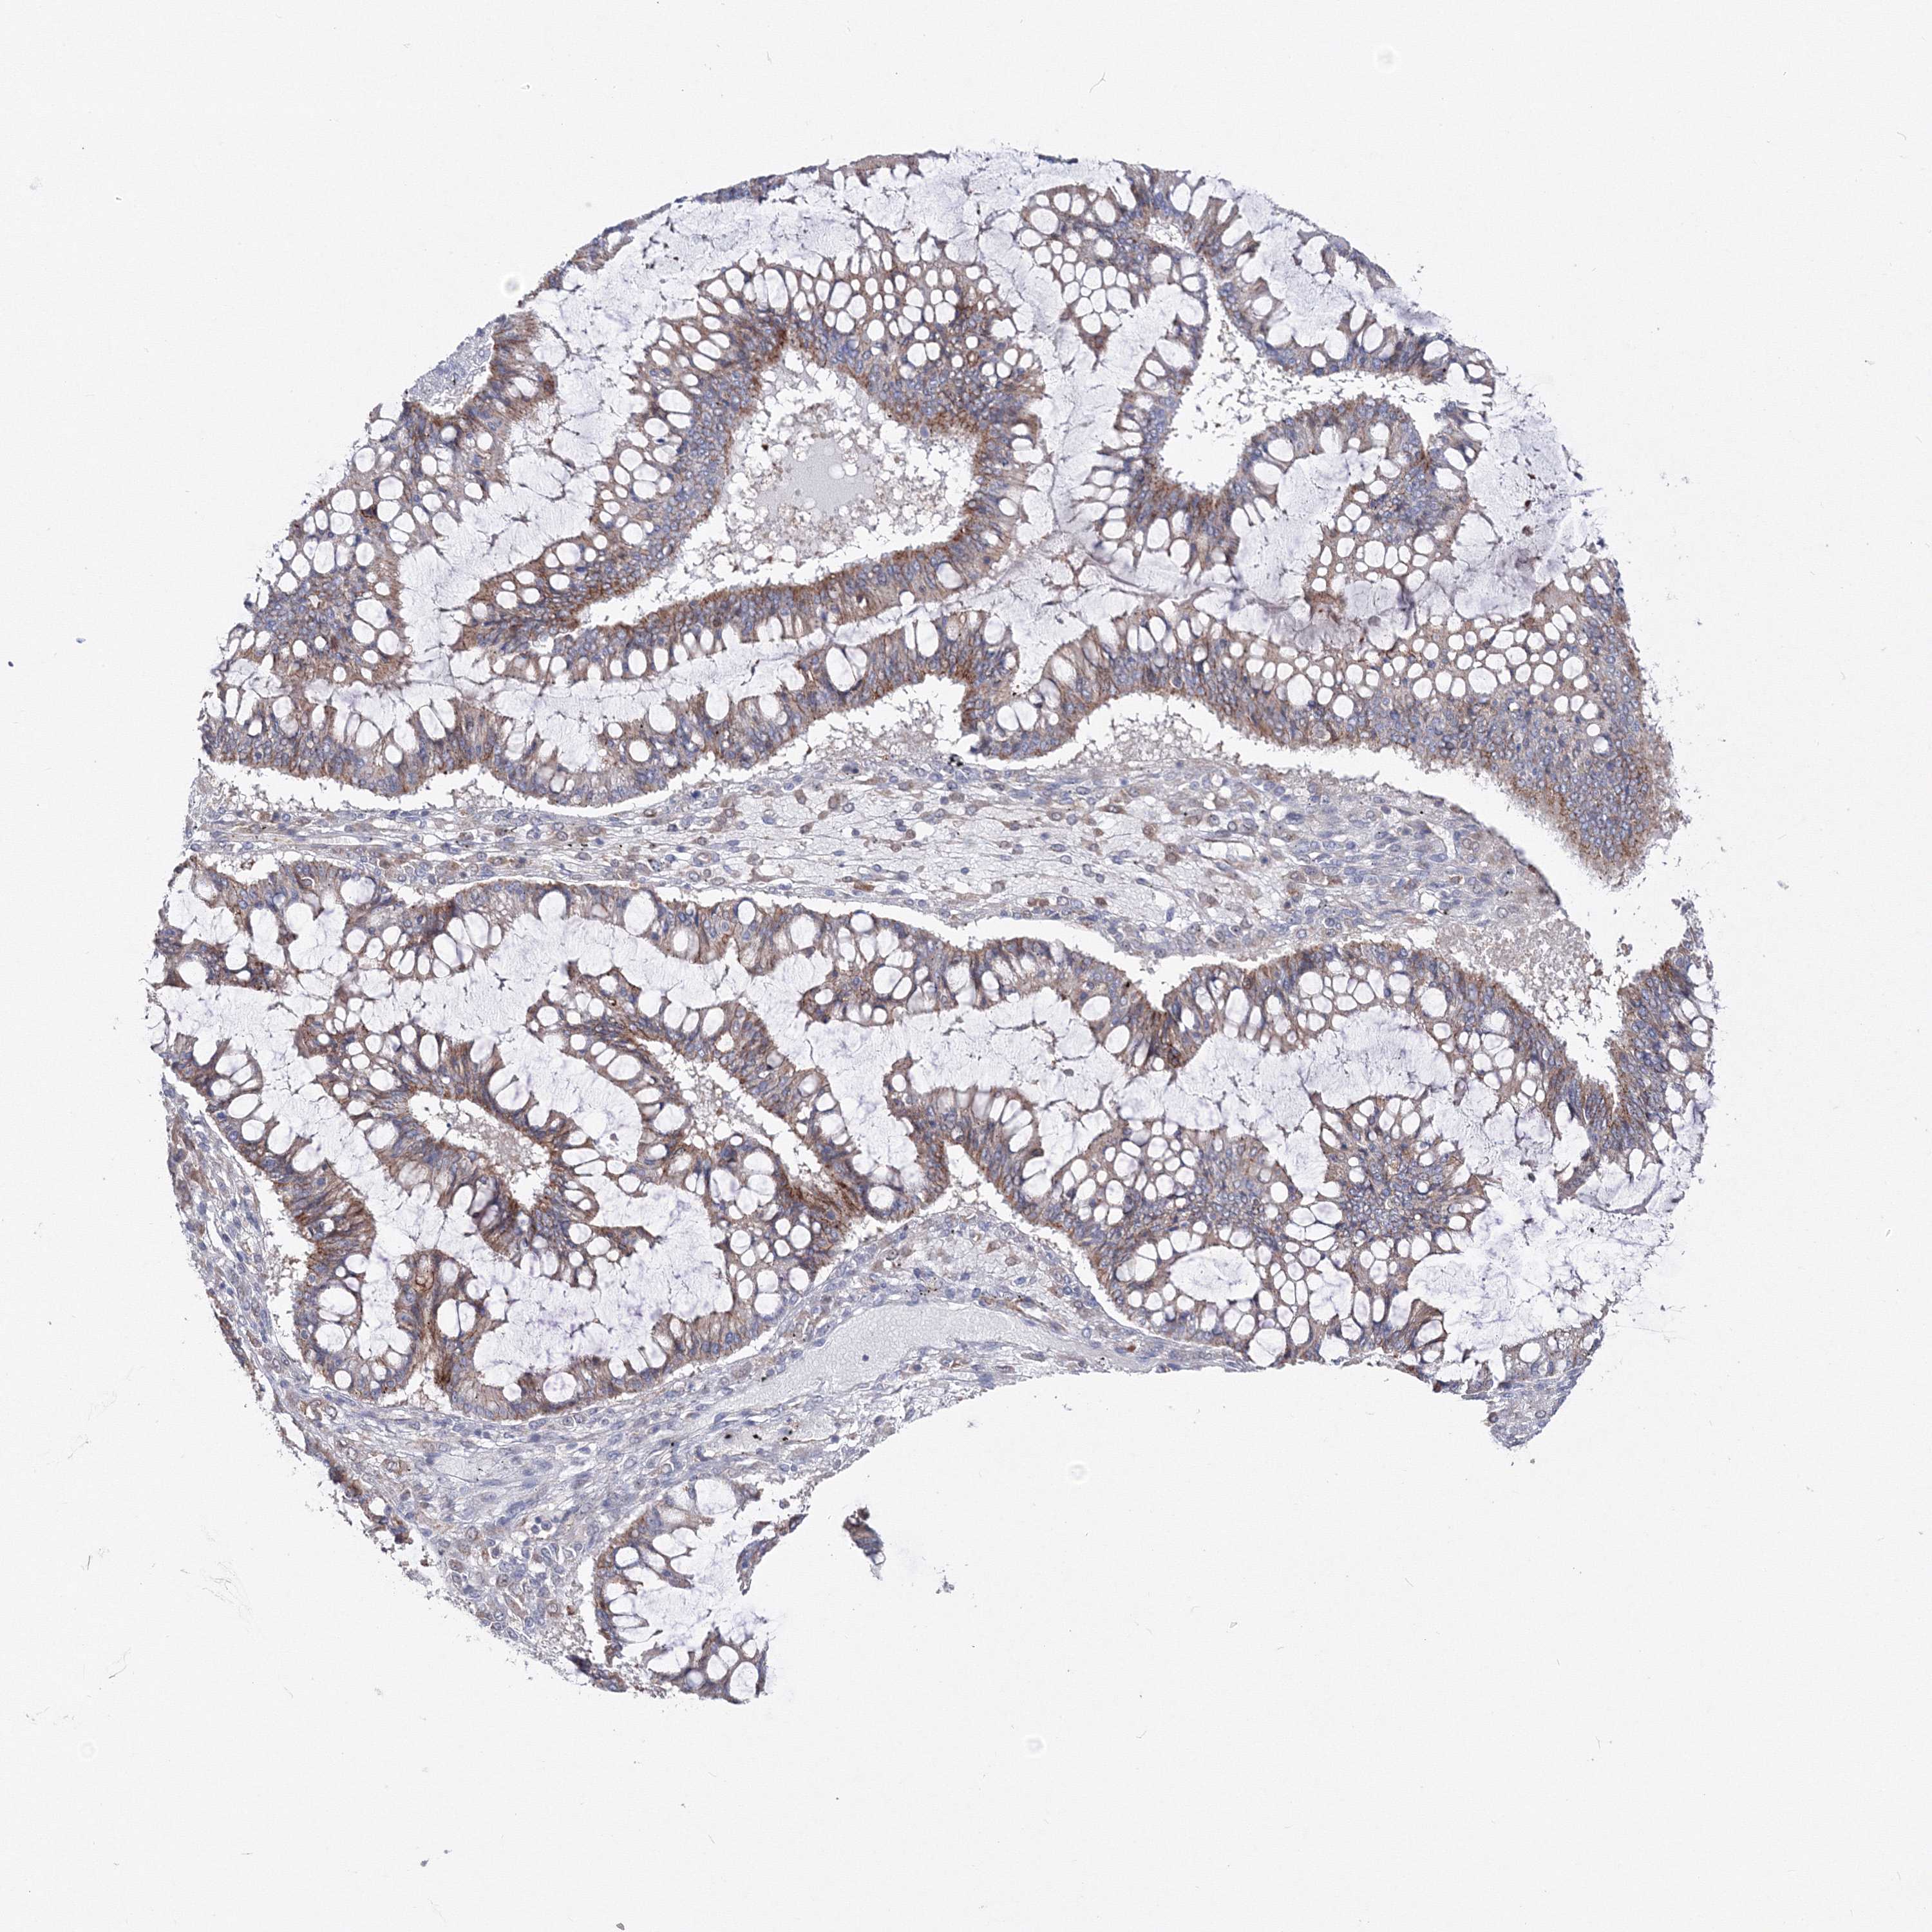

OVARIAN CANCER - Protein expressioni

A mouse-over function shows sample information and annotation data. Click on an image to view it in a full screen mode. Samples can be filtered based on level of antibody staining by selecting one or several of the following categories: high, medium, low and not detected. The assay and annotation is described here.

Note that samples used for immunohistochemistry by the Human Protein Atlas do not correspond to samples in the TCGA dataset.

Antibody stainingi

Antibody staining in the annotated cell types in the current human tissue is reported as not detected, low, medium, or high, based on conventional immunohistochemistry profiling in selected tissues. This score is based on the combination of the staining intensity and fraction of stained cells.

Each image is clickable and will lead to virtual microscopy that enables deeper exploration of all samples and also displays staining intensity scores, fraction scores and subcellular localization as well as patient and tissue information for each sample.

Antibody CAB034422

Staining

High

Medium

Low

Not detected

Intensity

Strong

Moderate

Weak

Negative

Quantity

>75%

75%-25%

<25%

None

Location

Nuclear

Cytoplasmic/membranous

Cytoplasmic/membranous,nuclear

Cystadenocarcinoma, serous, NOS

Carcinoma, endometroid

Cystadenocarcinoma, mucinous, NOS

Carcinoma, NOS